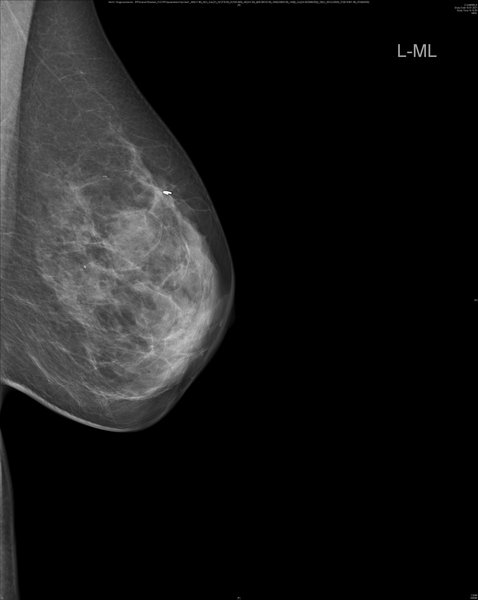

Bei rund einem Drittel der Brustkrebspatientinnen, die eine sogenannte neoadjuvante, der Operation vorgeschaltete Chemotherapie erhalten, bildet sich der Tumor vollständig zurück. Operiert werden sie bislang trotzdem, denn erst die Gewebeentnahme und -analyse bei der Operation zeigt eindeutig, ob alle Krebszellen abgestorben sind. Einen Ausweg aus dieser Problematik könnte ein lernender Algorithmus bieten, der gleichzeitig mehrere Faktoren berücksichtigt. Er ermöglicht laut ersten Studienergebnissen eine zuverlässige Diagnostik, wie Wissenschaftler des Brustzentrums der Universitäts-Frauenklinik Heidelberg unter anderem mit Kollegen vom MD Anderson Cancer Center, Houston, USA, und Royal Marsen Hospital, London, Vereintes Königreich, aktuell in einem Highlight-Artikel im European Journal of Cancer berichten. Sie testeten im Rahmen der RESPONDER-Studie verschiedene Methoden des maschinellen Lernens anhand der Daten dreier in den letzten Jahren publizierter Studien aus Heidelberg, den USA und Südkorea mit insgesamt 457 Brustkrebspatientinnen. „Mit Hilfe dieses intelligenten Diagnostikwerkzeugs könnte zukünftig rund einem Drittel der Frauen mit vorgelagerter Chemotherapie und gutem Ansprechen die anschließende Operation erspart werden," so Studienleiter Prof. Dr. Jörg Heil, Leiter des Brustzentrums an Universitätsklinikum und Nationalem Centrum für Tumorerkrankungen Heidelberg. Bevor es soweit ist, muss der Algorithmus allerdings seine Zuverlässigkeit noch in einer weiteren Studie unter Beweis stellen.

Die Frage, wie gut die Chemotherapie im Vorfeld der Operation angeschlagen hat, lässt sich – das haben aktuelle Studien gezeigt, die von den Heidelberger Wissenschaftlern federführend durchgeführt wurden – weder mit bildgebenden Untersuchungen noch mittels Biopsie zweifelsfrei beantworten. „Das Problem bei der alleinigen Biopsie ist, dass das Tumorgewebe bei Brustkrebs häufig heterogen ist und entsprechend uneinheitlich auf die Therapie anspricht", erläutert Seniorautor Heil. „Nur weil die Gewebeprobe aus der Biopsie keine Krebszellen mehr enthält, heißt das nicht, dass der gesamte Tumor abgestorben ist." Eindeutige Klarheit bringt bislang erst die Untersuchung des bei der Operation entnommenen Gewebes. Die Behandlungsrichtlinie sieht daher vor, dass alle Frauen dem ursprünglichen Tumor entsprechend operiert werden. So wird Gewebe entnommen, obwohl möglicherweise gar kein Tumor mehr vorhanden ist.

Um den Frauen mit sehr gutem Ansprechen auf die Chemotherapie eine unnötige Operation zu ersparen, machten sich die Heidelberger Wissenschaftler Methoden des Maschinellen Lernens zunutze. Dabei wird ein rechnergestütztes System darauf trainiert, aus der gemeinsamen Analyse verschiedener Faktoren Zusammenhänge zu erkennen und darauf basierend eine belastbare Diagnose zu stellen. In den Algorithmus, der sich am zuverlässigsten erwies, fließen insgesamt 27 Faktoren ein, darunter unter anderem Alter der Patientinnen, Merkmale des Tumors und die Ergebnisse einer bestimmten Art der Biopsie (Vakuum-assistiert). In einer internen wie externen Überprüfung mit Patientendaten aus den verwendeten Studien übersah das System keinen verbliebenen Tumor, was für eine hohe diagnostische Sicherheit des Algorithmus spricht.